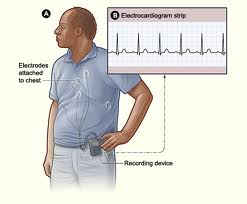

- Electrocardiogram (ECG or EKG)

- Heart Monitoring (Holter Monitor, Event Monitor,Implantable Loop Recorder)

A type of portable heart monitor that is a small electrocardiogram (EKG) device worn in a pouch around the neck or waist. A Holter monitor keeps a record of the heart rhythm, typically over a 24-hour period, and the patient keeps a diary of activities and symptoms. The EKG recording is then correlated with the person's activities and symptoms. This type of test is useful for identifying heart disturbances that are sporadic and not readily identified with a resting EKG.

This test is useful for evaluating patients who are experiencing palpitations, passing out spells, and dizziness. Occasionally, it may diagnose conditions such as atrial fibrillation, which the patient experiences as an irregular heart beat. This is important to identify as untreated atrial fibrillation is a common cause of stroke. Since starting a dedicated weight loss program in 2010 at California Cardiovascular Care, Dr. Christodoulou has helped more than 200 of his patients lose 30-200 lb. Many of these patients started out with multiple medications for treatment of conditions such as diabetes, hypertension, coronary artery disease, obstructive sleep apnea and chronic fatigue. These are mostly conditions caused by, or exacerbated by, being overweight. Weight loss has enabled these patients to either stop medication and/or drastically reduce the amounts of medication needed to maintain their health. This is achieved in most cases through diet alone. The process starts with biometric measurments of your body, and a blood test to determine various indices including measurments of insulin resistance, and cholesterol particle size testing. A diet is then specifically designed for you that generally achieves an immediate weightloss of 12-20 lb within six weeks. Thereafter, adjustments at regular intervals are made to help achieve, or maintain your goal weight.